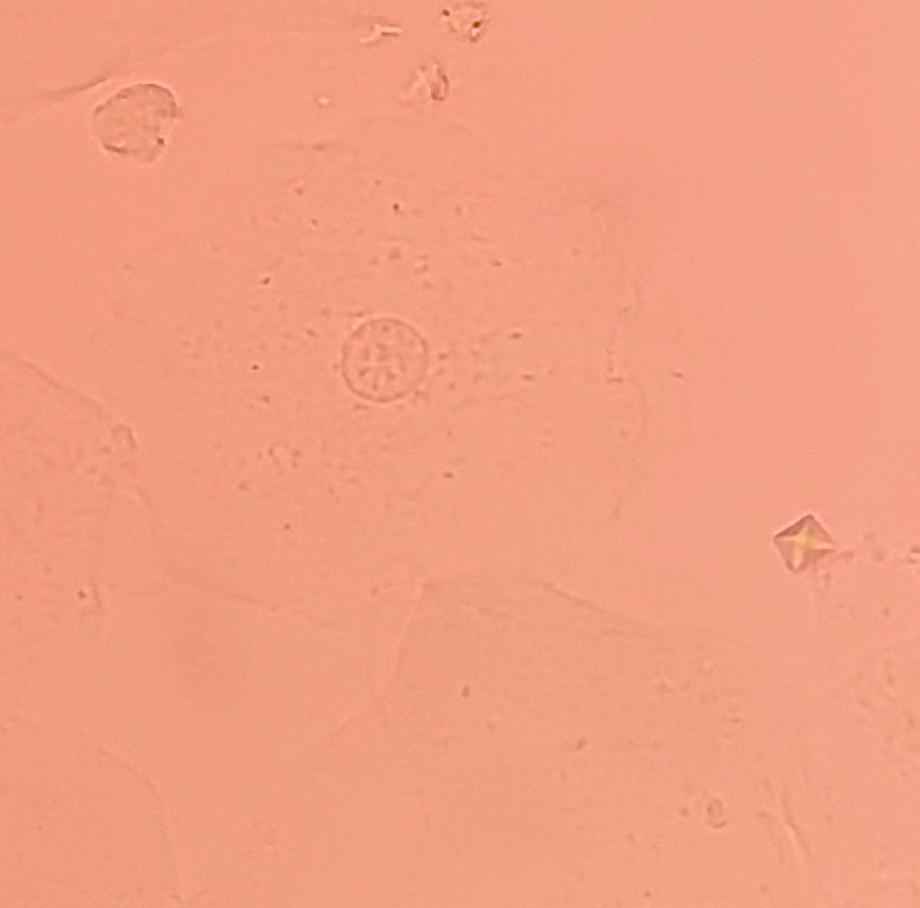

본문 시작 요 pH 측정 임상병리학과 385 2025-05-19 요 pH를 측정해본 후 산성뇨, 염기성뇨와 관련된 질병에 대해 알아보는 시간을 가졌습니다 목록 이전요시험지 테스트 다음 환자 검체를 이용한 요침사 검경 & 회식 만족도조사 만족도 조사 이 페이지에서 제공하는 정보에 대하여 만족하시나요? 매우만족 만족 보통 불만족 매우불만족